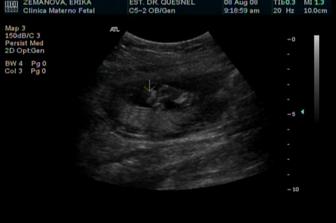

Jo a abych nezapomněl - jak pořád naši mluvili o tom focení, tak jsme tam nakonec fakt zase byli. Měli to domluvené na jedenáctou, tak jsem maminu preventivně vzbudil už ve čtyři ráno (hra na kopanou - pravidla viz výše). Mám radost, jak jsem je všechny převezl - od toho posledního focení jsem jim pěkně vyrostl, takže a) mě teď musí fotit po částech a b) tím pádem rozpatlají tu studivou věc mamce po celém bříšku, chichi. Říkali, že se na mě podívají zase za měsíc. Takže mám dost času na to, abych si na ně zase něco pěkného vymyslel.